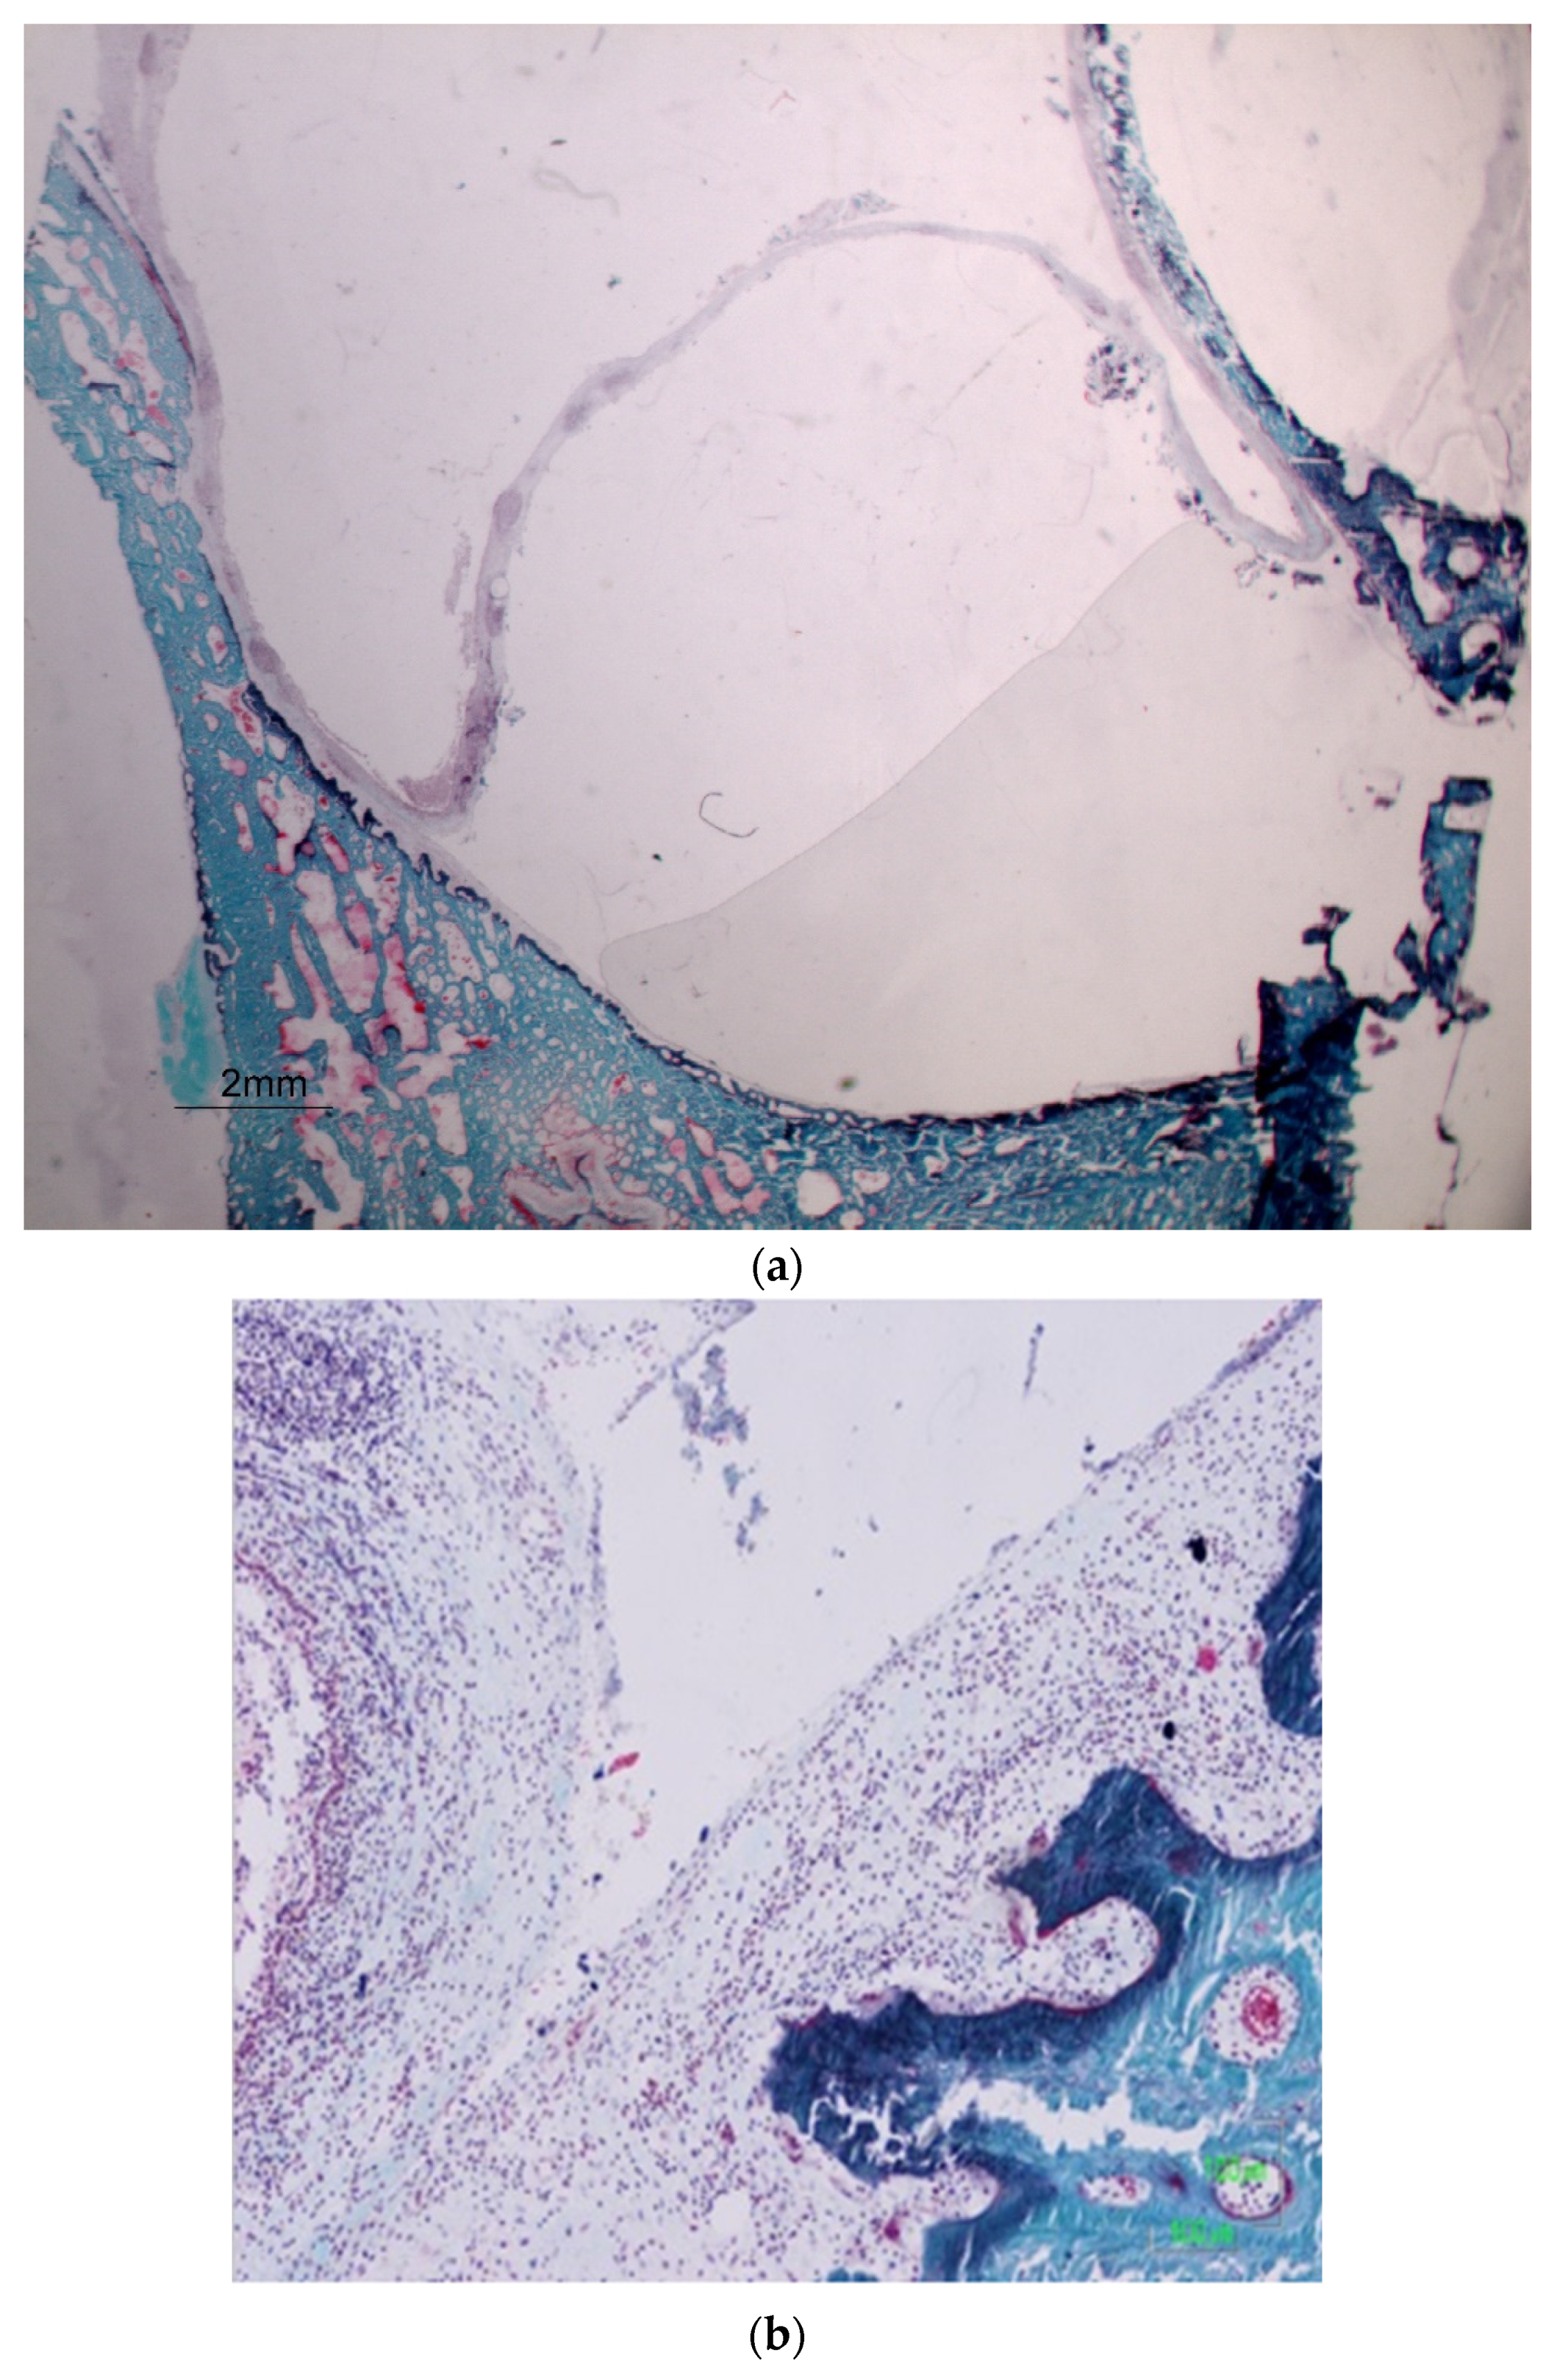

- Staining: The sections were stained using Goldner’s Trichrome, a method that highlights the difference between osteoid (unmineralized bone) and mineralized bone, as well as providing insights into the cell morphology.

- Microscopic Analysis: The stained sections were analyzed using a Nikon digital camera Sight DS-SMC attached to a Nikon Eclipse 90i optical microscope.